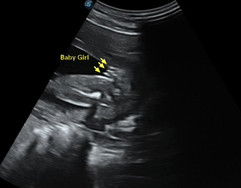

gender (25w4d)

boy ke girl ? doktor dah bgtau , tp saje nak korang teka dari mata korang pulak . sbb byk sgt dorang ckp boleh kena scam dengan baby . heheheeh

Girl ni. Saya punya pulak nmpk 3 line mcm ni masa 21w. Harap tak scam lah

girl,klu boy ada pistolnye hehe

burger